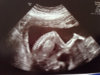

Legger ved et par bilder. Hun sto slik med hodet trykket inn i livmorveggen og rumpa til værs på halvparten av bildene